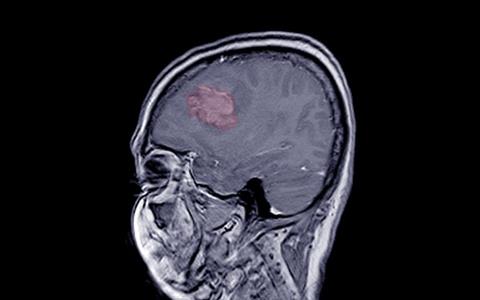

Meningioma is the most common type of primary brain tumour. Standard of care for treating meningioma cancers is either surgery or radiation therapy, the researchers stated. Participants (median patient age was 67), received a total of four infusions of 177Lu-Dotatate every eight weeks.